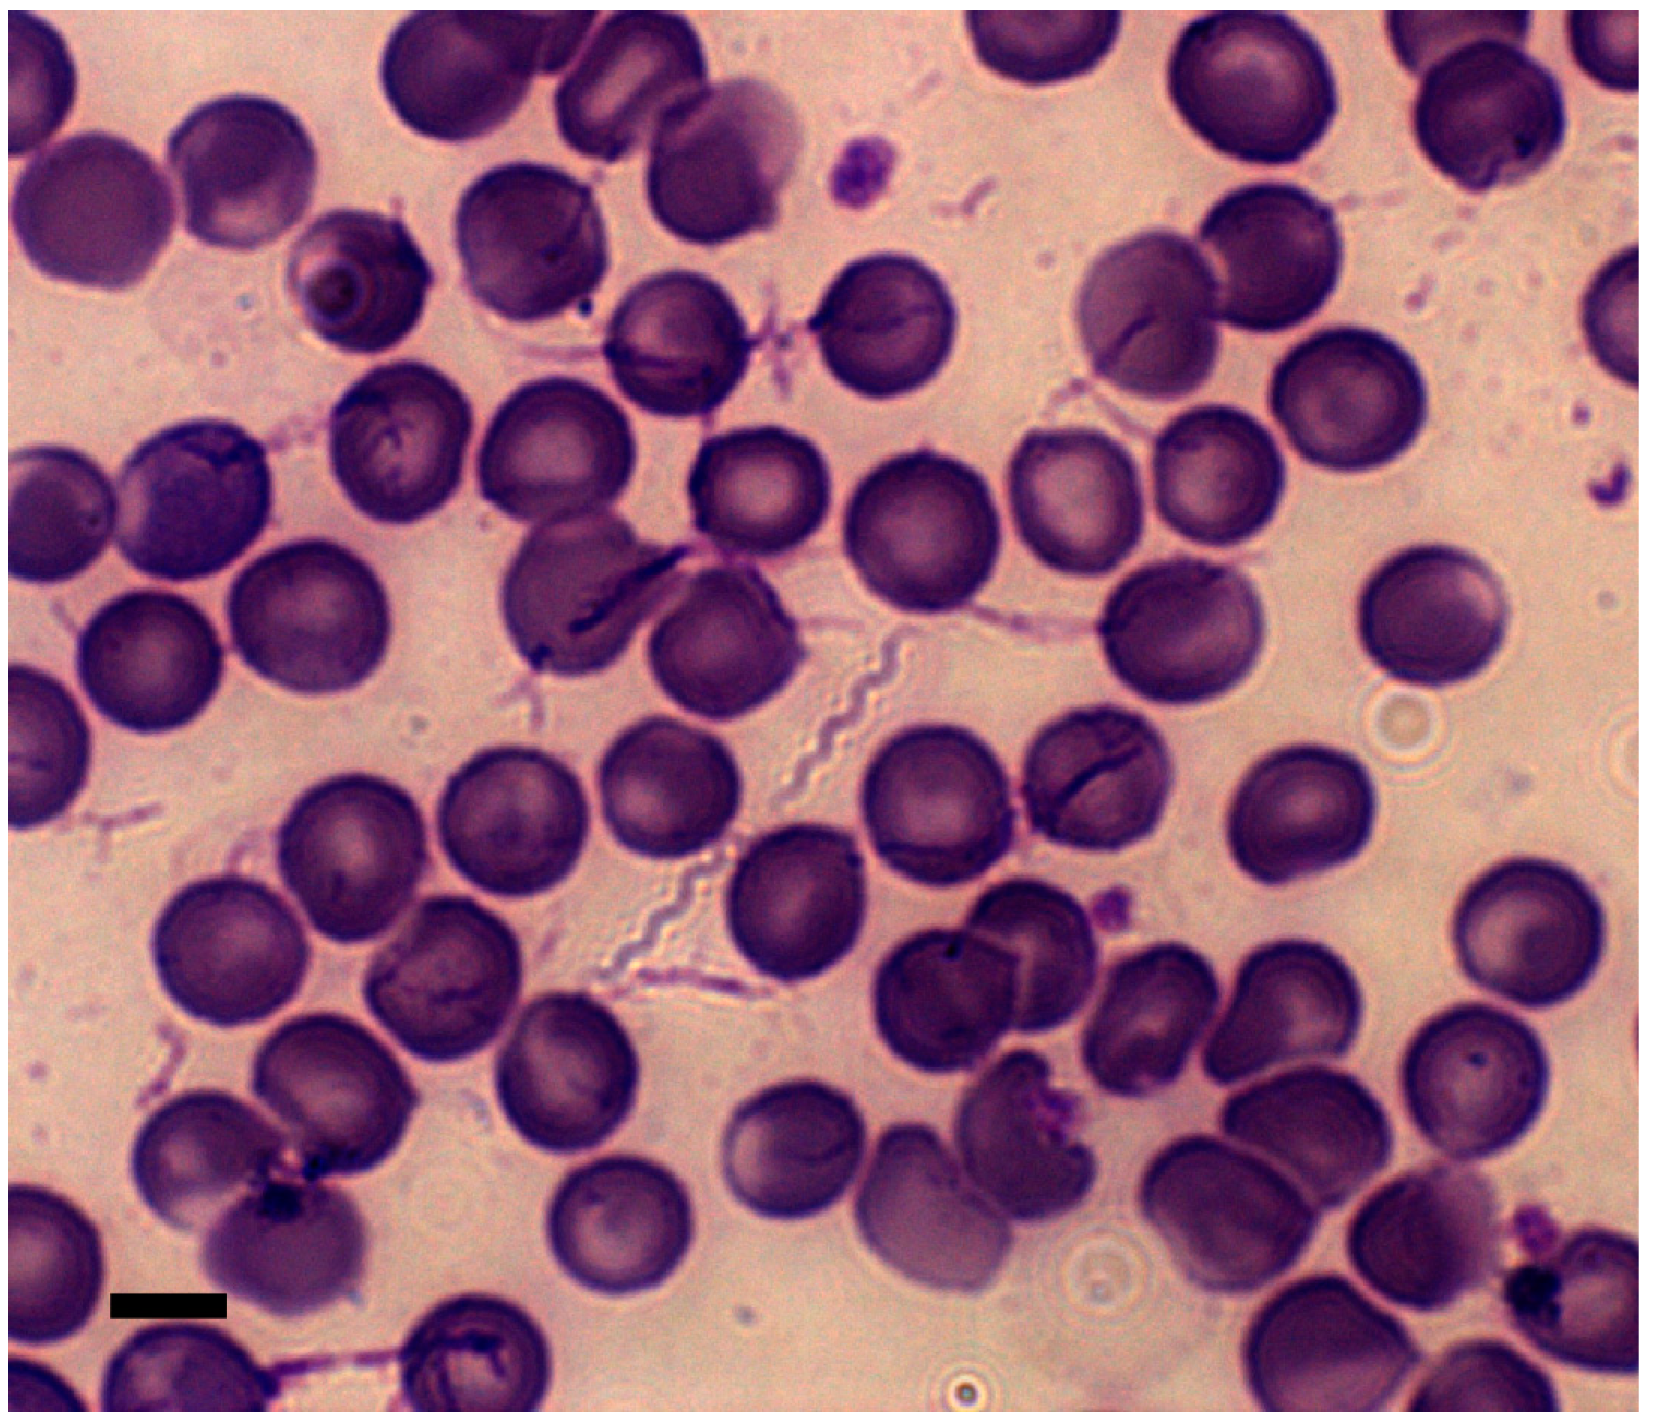

Лептоспиры: фотографии удивительных микроорганизмов